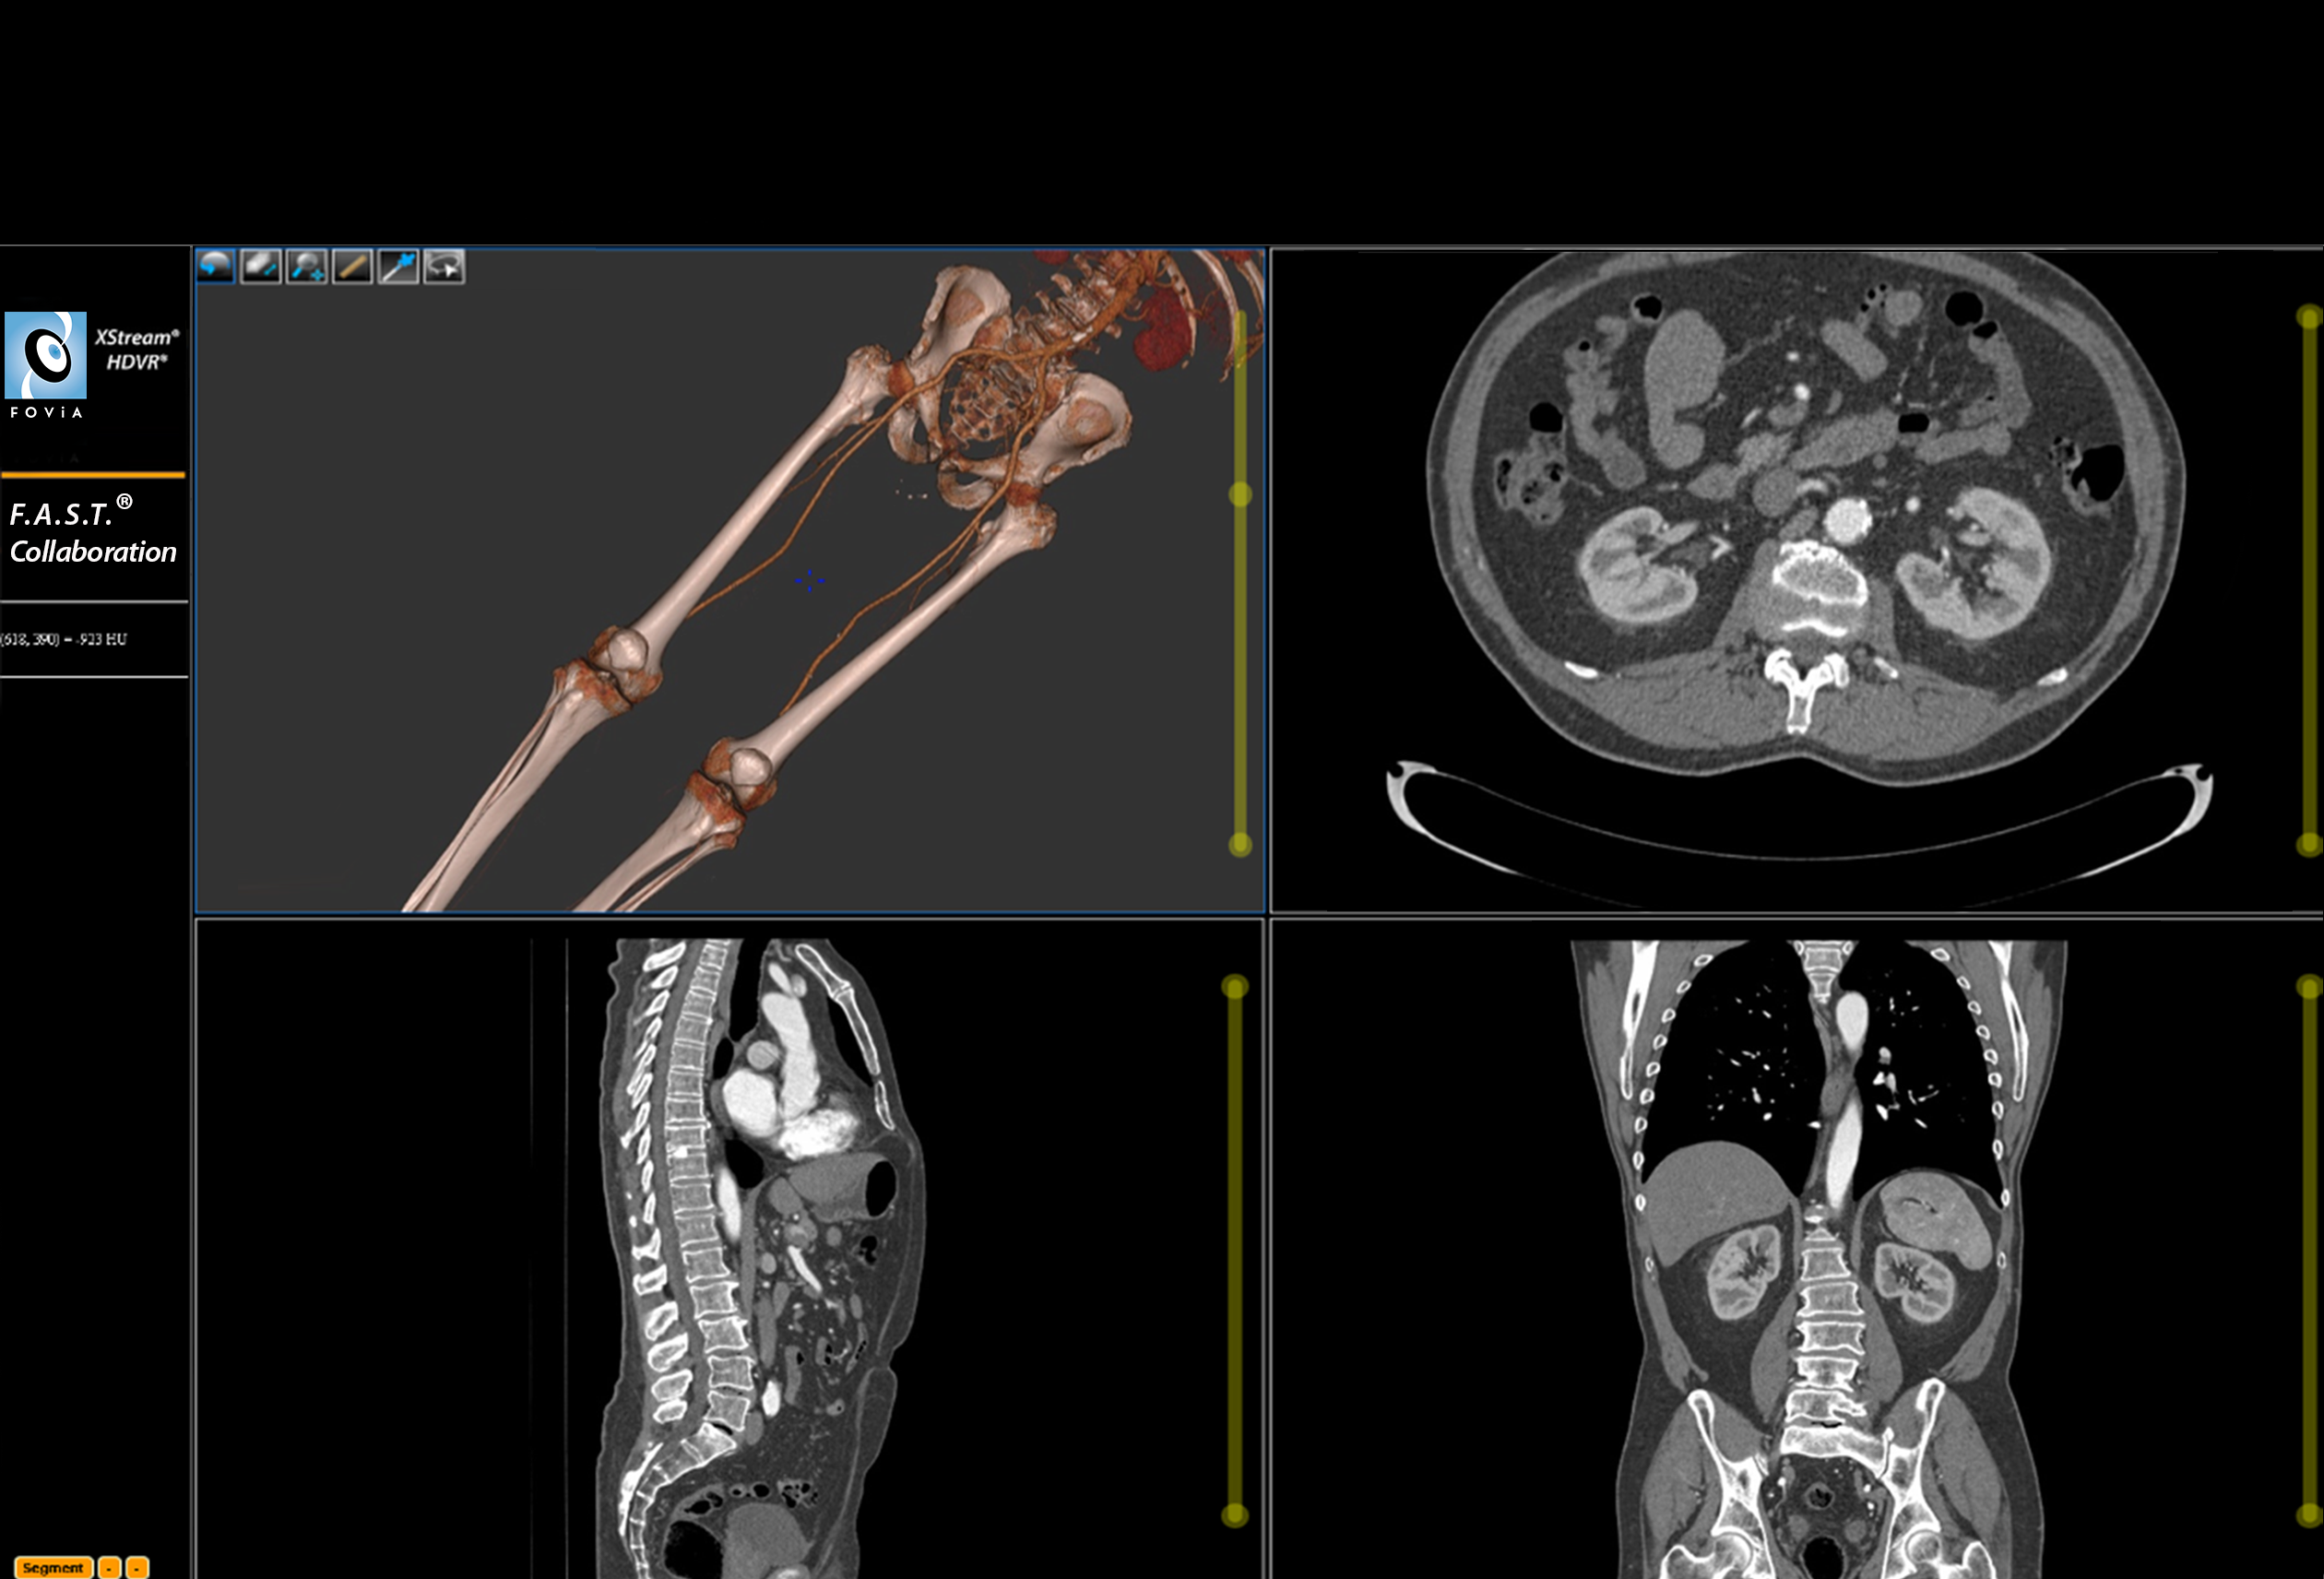

F.A.S.T. Collaboration Workflow

F.A.S.T. Collaboration Workflow